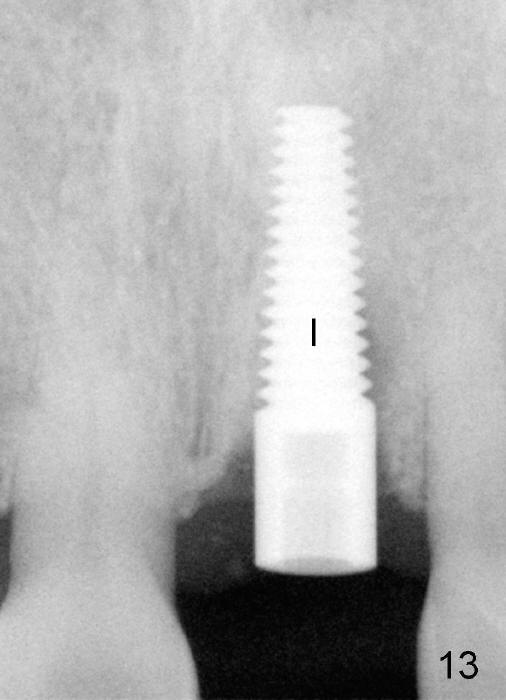

A 60-year-old lady had an abscess mesial to #9 six years ago (Fig.1,2 <), treated as a perio lesion by laser (Fig.3) and osseous surgery without bone graft (Fig.6, followed by CT exam revealing semi-circumferential bone loss (Fig.4,5). When the perio treatment failed, attention was paid to endo aspect (Fig.7-9). In fact the pulp was found to be vital when access to root canal therapy was made. As expected, the treatment failed again. The palatal fistula persisted. The infection was suspected to be a source of remote immediate implant site (#30). The tooth #9 was extracted. It appears that there is a semilunar crack line in the linguomesial root (Fig.12). When the socket healed 2 weeks post extraction (Fig.10), the #30 buccal defect was debrided with bone graft. There was no bone resorption 4 weeks post extraction (Fig.11); a 4.5x17 mm implant was placed (Fig.13-15). An immediate provisional was fabricated (Fig.16-18). Fig.19,20 were taken 3 months post implantation and 7 months post cementation, respectively. Dense bone forms around the implant coronally 4 years 5 months post cementation (Fig.21), while the gingiva is healthy palatally (Fig.22) and buccally (Fig.23).